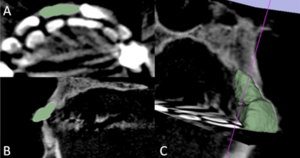

Patient-specific Interactive Software Module for Virtual Preoperative Planning and Visualization of Pedicle Screw Entry Point and Trajectories in Spine Surgery

Publication: Neurol India. 2018 Nov-Dec;66(6):1766-70. PMID: 30504578 | PDF Authors: Muralidharan V, Swaminathan G, Devadhas D, Joseph BV. Institution: Department of Neurological Sciences, Christian Medical College, Vellore, Tamil Nadu, India. Abstract: BACKGROUND: Lumbar pedicle screw insertion involves a steep learning curve for novice spine surgeons and requires image guidance or navigation. Small volume centers may be handicapped by the lack of cost-effective user-friendly tools for preoperative planning, guidance, and decision making. OBJECTIVE: We describe a patient-specific interactive software module, pedicle screw simulator (PSS), for virtual preoperative planning to determine the entry point and visualize the trajectories of pedicle screws. MATERIALS AND METHODS: The PSS was coded in Python for use in an open source image processing software, 3D Slicer. Preoperative computed tomography (CT) data of each subject was loaded into this module. The entry-target (ET) mode calculates the ideal angle from the entry point through the widest section of the pedicle to the desired target in the vertebral body. The entry-angle (EA) mode projects the screw trajectory from the desired entry point at a desired angle. The performance of this software was tested using CT data from four subjects. RESULTS: PSS provided a quantitative and qualitative feedback preoperatively to the surgeon about the entry point and trajectories of pedicle screws. It also enabled the surgeons to visualize and predict the pedicle breach with various trajectories. CONCLUSION: This interactive software module aids in understanding and correcting the orientation of each vertebra in three-dimensions, to identify the ideal entry points, angles of insertion and trajectories for pedicle screw insertion to suit the local anatomy. |

EA mode of pedicle screw trajectory planning in a patient with high grade L5-S1 spondylolisthesis. (a) Correction of vertebra rotation. (b) Marking of fiducials. (c) Desired trajectory for selected entry point and angle. (d) Marking of the entry and target fiducials for desired iliac wing screw. (e) Ideal trajectory of iliac wing screw and panel displaying the angle of screw trajectory using entry-target mode. |